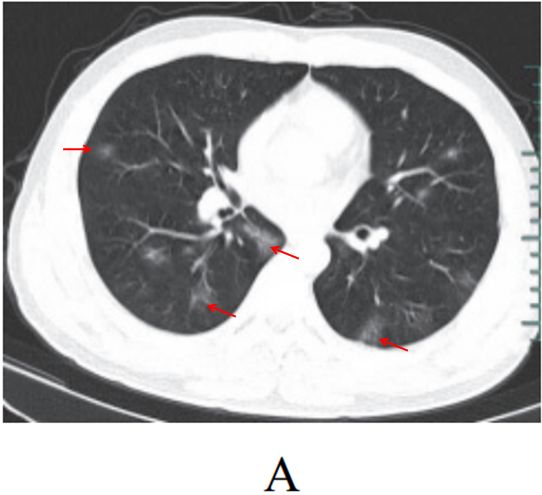

影像学表现:

(1)病变多分布于两肺中内带,可见沿支气管血管束分布的斑片、絮片、条索状影(图 3-9),出现树芽征。

图片